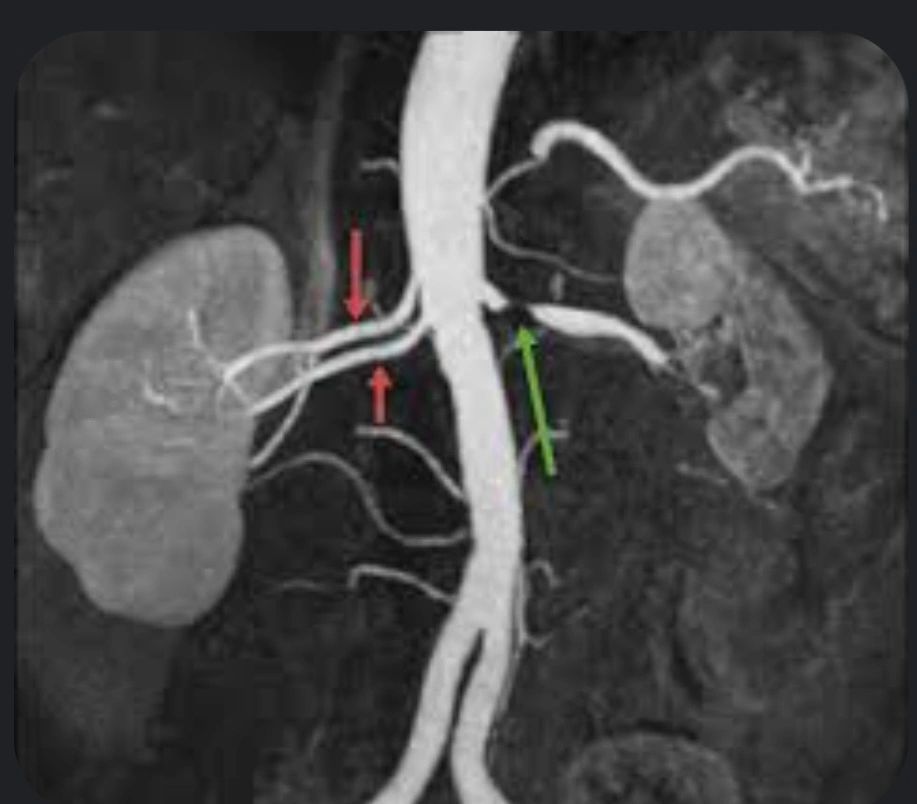

Angiorresonancia (MRA) 90–100% 85–94% Útil si alergia al yodo o ERC

C. MRA

Excelente resolución sin yodo

Riesgo de fibrosis sistémica nefrogénica con gadolinio en ERC severa